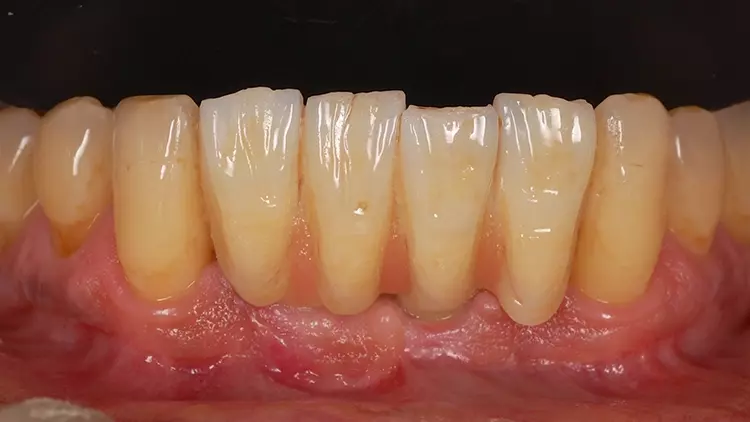

Als Interimsversorgung wurden herausnehmbare, klammerverankerte Prothesen aus Methylmethacrylat verwendet. Nach der dreimonatigen Einheilzeit erfolgten die Implantatfreilegung und die Versorgung mit Einheilkäppchen. Bei der Freilegung der Implantate und der Versorgung mit Einheilkäppchen sowie zum Zeitpunkt der Abformung mit den Abutments in situ lag eine reizlose klinische Situation ohne Anzeichen einer Entzündung im Implantatbereich vor (Abb. 4 und 5).

Der fehlende Zahn 24 wurde ebenfalls mittels eines Semados RS Implantats (BEGO Implant Systems GmbH & Co. KG) mit einer Länge/einem Durchmesser von 4,1/10,0 mm und einer monolithischen Zirkonoxidkrone ersetzt (3D Pro). Die klinische Situation konnte im Rahmen einer Nachuntersuchung im September 2022, fast zweieinhalb Jahre nach der Versorgung im Mai 2020 als sehr gut bezeichnet werden (Abb. 17-20).